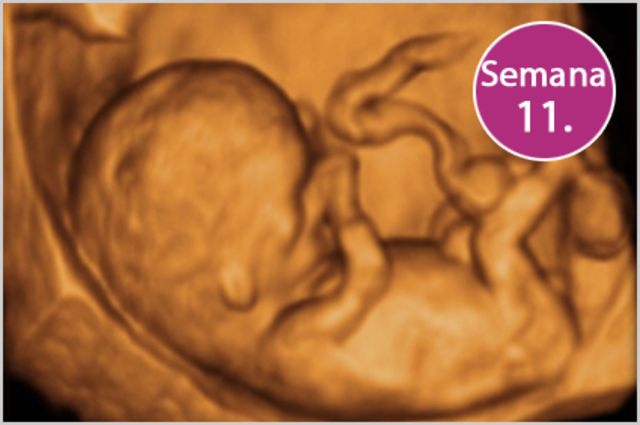

• 11 semanas. Características externas

11 semanas. Características externas

-La flexión cervical es de cerca de 8 grados

-Comienza a desarrollarse el puente de la nariz

• 11 semanas. Características internas

11 semanas. Características internas

-Se excreta orina hacia el líquido amniótico

-La musculatura gástrica puede contraerse

-Los linfocitos T migran hacia la circulación

-Aparece el coloide en los folículos tiroides